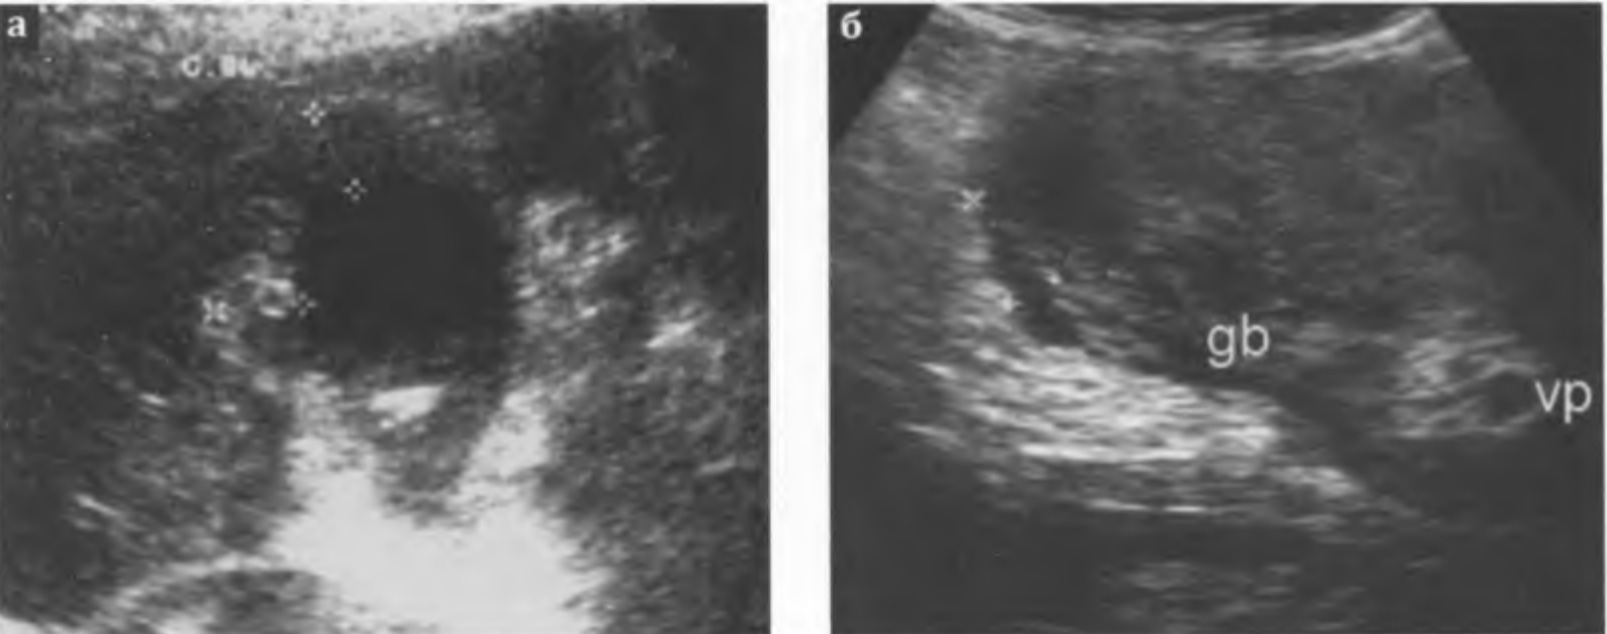

Рис. 3.9 а, б. Гангренозный холецистит:

а - стенка желчного пузыря неравномерно утолщена, контур неровный, нечеткий, эхогенность стенки неравномерно снижена, с анэхогенными включениями (+...+); определяется инфильтрация окружающих тканей - неравномерное снижение их эхогенности с гипо- и анэхогенными включениями;

б - ложе желчного пузыря ячеистой структуры, без четкой границы сливается с изображением стенки пузыря; вокруг желчного пузыря (gb) определяется скопление жидкости (+...+); vp - воротная вена.